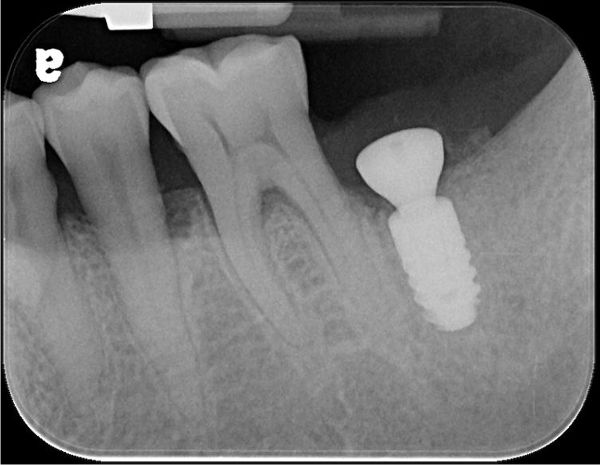

植牙後X光確認

術後X光